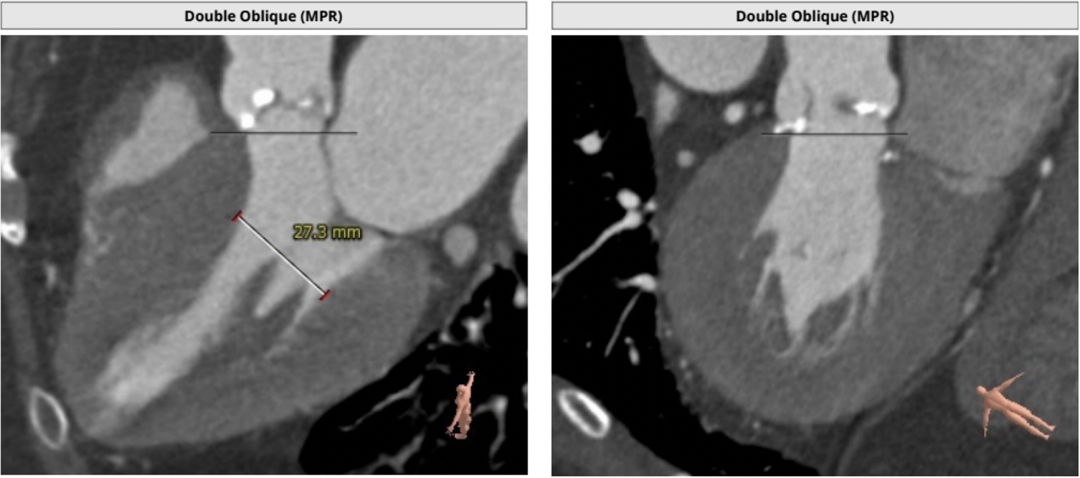

左室大小尚可,心尖部位薄弱

左室小,心肌肥厚